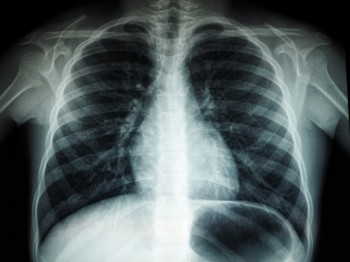

An X-ray of a chest

Up to £1.2m has been awarded to Cheshire and Merseyside to accelerate the implementation of an AI imaging and support tool which can analyse chest X-ray images and identify possible signs of lung cancer.

The tool, which will be rolled out to nine acute and specialist NHS trusts across Cheshire and Merseyside, can identify nodules and masses on chest X-rays to both ensure those patients can be prioritised and reduce the administrative burden on clinical staff.